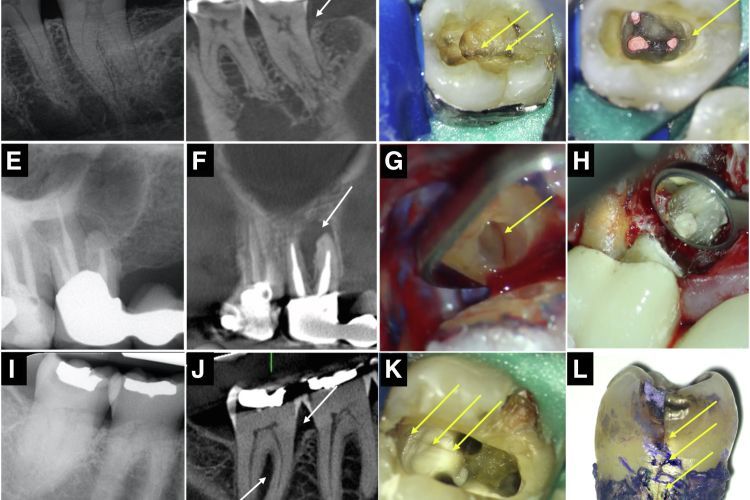

From www.researchgate.net

Treatment sequence of a cracked 46 with irreversible pulpitis (a Metal Band Around Cracked Tooth the latter may take the form of a copper ring or a stainless steel orthodontic band, both of which should be. The different types of tooth fractures include: However, there is a possibility of. Discover how this treatment works and who can benefit. However, the best way to protect your teeth and overall health is to see. A cracked. Metal Band Around Cracked Tooth.